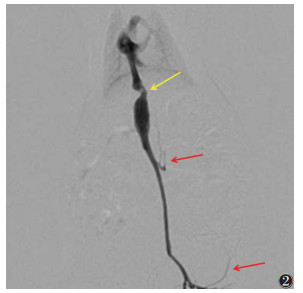

2 结果 2.1 成模情况对照组存活15只,假手术组1、4、8、12周亚组分别存活14、14、15、15只,对照组及假手术组活动如常、反应机警,DSA均无阳性表现。模型组各亚组均存活14、13、13、13只,存活大鼠均成模,大鼠术后毛色灰暗无光泽,活动逐渐减少、反应迟钝,肝后段下腔静脉管腔变窄,远端扩张,4周后见侧支循环逐渐形成(图 2)。

| 注:肝后段下腔静脉管腔变窄(黄箭),远端扩张,见侧支循环形成(红箭) 图 2 模型组4周DSA图 |